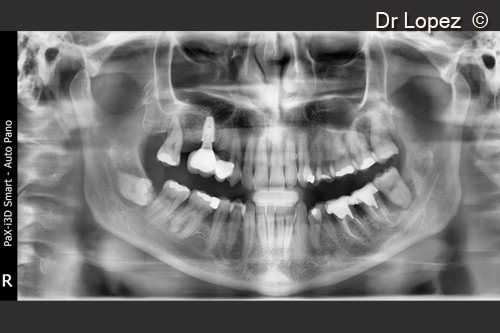

A male patient (50 years old) shows a severe vertical atrophy in position 16

1. TC at starting point. Severe vertical atrophy on 16 site

9. Final OPT